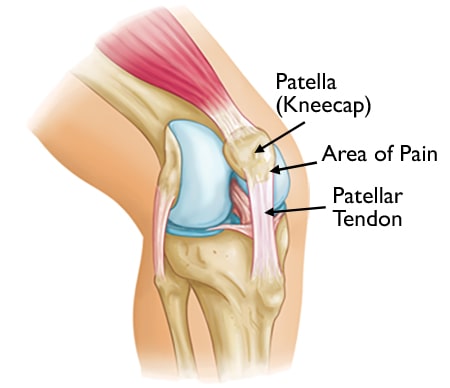

knee anatomy and Jumper's knee

Jumper's knee symptoms occur where the patellar tendon attaches to the patella.

Jumper's knee refers to pain that occurs in the lower portion of the patella (kneecap). These painful symptoms can range from mild to severe.

Repetitive contraction of the quadriceps muscles in the thigh can stress the patellar tendon where it attaches to the kneecap, causing inflammation and tissue damage (this condition is also known as patellar tendinitis).

In growing children, the patellar tendon attaches to the growth plate of the kneecap, and repetitive stress on the tendon can irritate and injure the growth plate. This condition is referred to as Sinding-Larsen-Johansson disease.